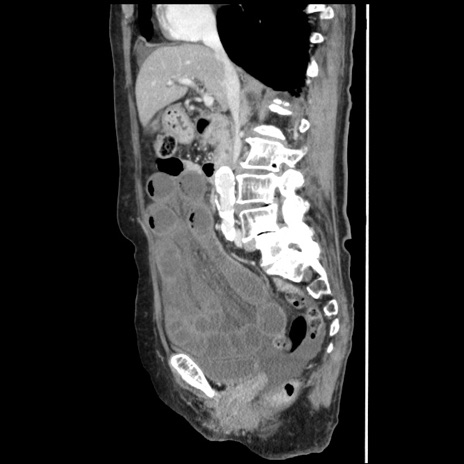

症例1(矢状断像)

【症例】80歳代女性

【主訴】腹痛

【現病歴】8時間前から腹痛あり来院。

【既往歴】糖尿病、脂質異常症、子宮体癌にて子宮全摘術

【身体所見】意識清明・会話良好だが腹痛で苦悶様、全腹部にわたって反跳痛と圧痛あり

【データ】WBC 13600、CRP 0.14、LDH 224、CK 90